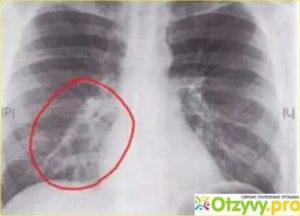

Рентгеновский снимок по-разному отображает каждый орган, сердце человека вообще выглядит как световое пятно. Здоровые легкие имеют однородный цвет на снимке, если присутствует патология, она будет отображаться пятнами различной интенсивности. На легких очаги темного цвета говорят об отеке и воспалении.

Признаки бронхита на рентгене будут специфическими. Сам воспалительный процесс не определяется, но внимание стоит обращать на тени. Поскольку лучи проникают через стенку и воздушное пространство альвеол, при развитии заболевания будут виднеться кольцевые пятна. Также проявляется и хроническая форма.

Заподозрить бронхит на рентгеновском снимке можно по таким показателям:

- изменяется рисунок легких и сосудов (по виду напоминает разветвление у дерева);

- разрастание соединительной ткани определяется как сгущенные корни;

- в некоторых местах имеются спадания ткани органа.

Бронхит на рентгене выглядит, как чередующиеся зоны низкой и высокой воздушности. Детальному рассмотрению подлежат корни легких, поскольку происходит их деформация.

Именно эти изменения четко определяются на снимке, так же как и чрезмерное разрастание фиброзной ткани. Зная о том, как на рентгене выглядит бронхит, не стоит пытаться самостоятельно сделать расшифровку.